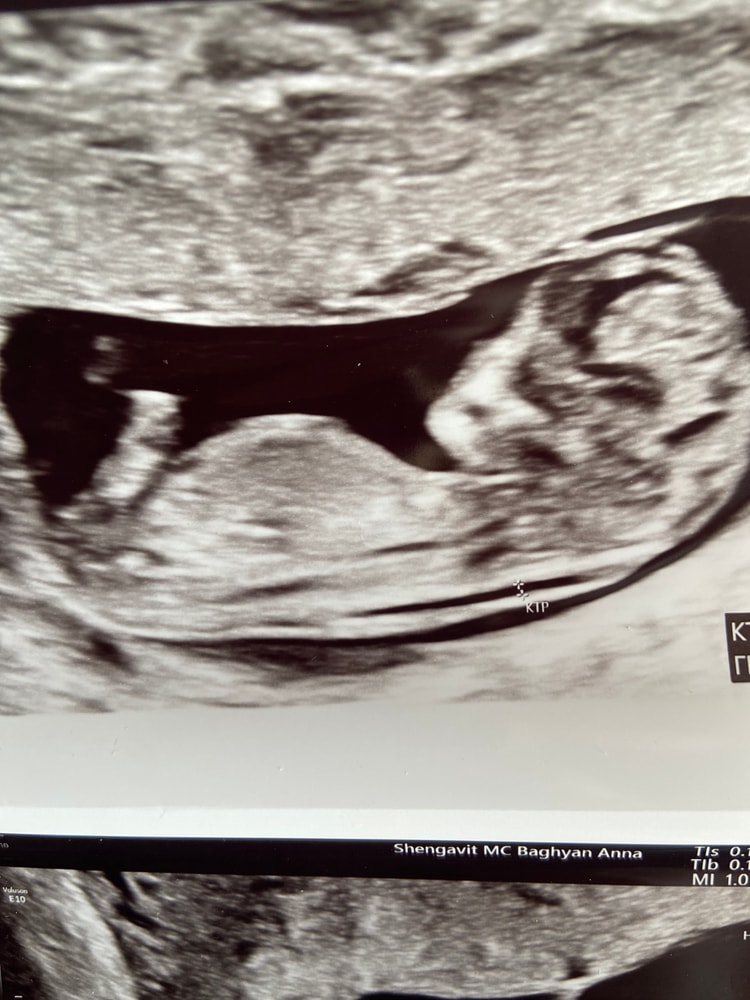

В 18 недель носовая кость 2.7 поставили гипоплазию

остальное все в порядке и соответствует сроков